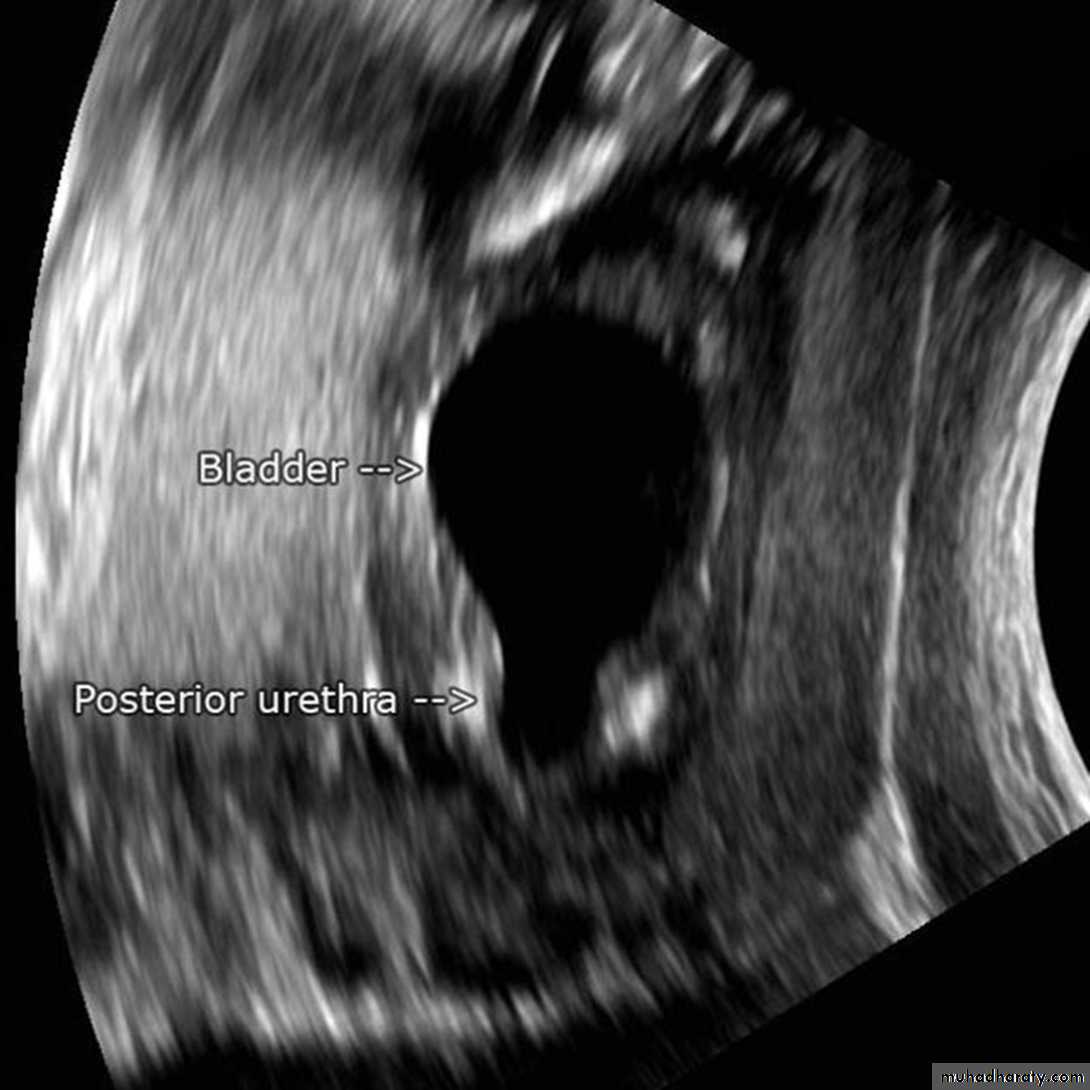

Ultrasonography; is the standard method for identifying hydronephrosis in infancy. Postnatal ultrasound imaging is usually deferred until day 3 of life, to allow for improvement in the relative oliguria, which could lead to underestimation of the degree of hydronephrosis.DIAGNOSIS

If prenatal US has shown a large or bilateral hydronephrosis, a follow-uprenal tract ultrasound scan should be performed soon after birth. If there

is a prenatal unilateral hydronephrosis (and the bladder is normal), the

scan is deferred until days 3–7 (to allow normal physiological diuresis to

occur, which may spontaneously improve or resolve hydronephrosis).

InvestigationUltrasound scan of kidneys and bladder.